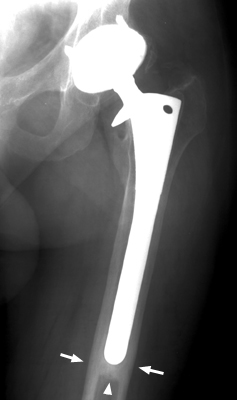

Diagnosis:Loosening prosthesis Discussion:Always associated with the presence of divergent radio-opaque lines, the pedestal sign is indicative of prosthetic loosening of the femoral stem in cementless total hip arthroplasty. The presence of radio-opaque lines within a radiolucent area, separated from the prosthetic tip by at least 2 mm, is defined as the "pedestal sign." References: